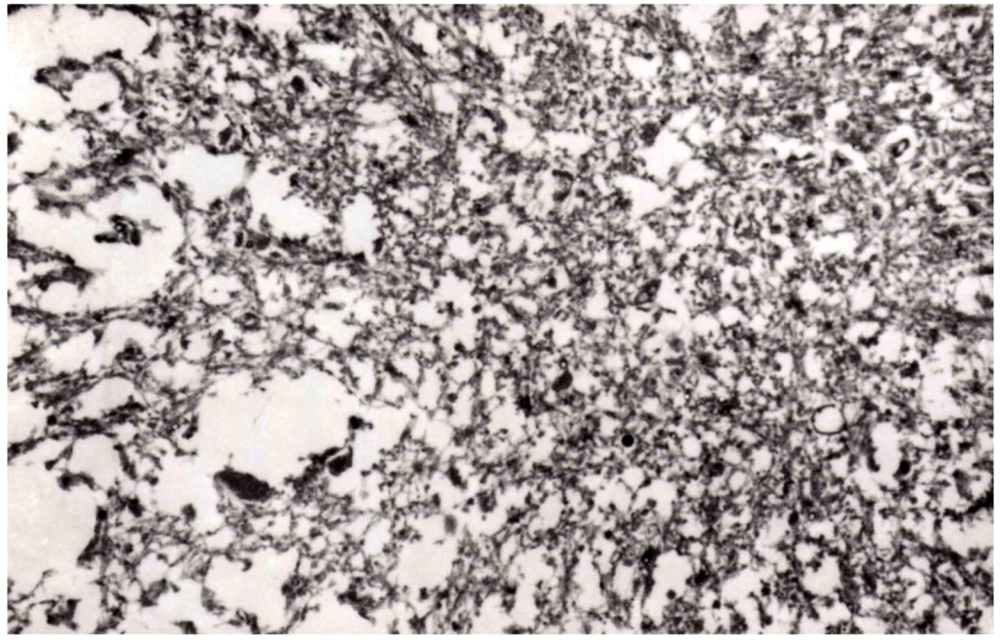

8. Neuropathology

- Liberski, P.P.; Sikorska, B.; Lindenbaum, S.; Goldfarb, L.G.; McLean, C.; Hainfellner, J.A.; Brown, P. Kuru: Genes, cannibals and neuropathology. J. Neuropathol. Exp. Neurol. 2012, 71, 92–103. [Google Scholar] [CrossRef]

- Hainfellner, J.; Liberski, P.P.; Guiroy, D.C.; Cervénaková, L.; Brown, P.; Gajdusek , D.C.; Budka, H. Pathology and immunohistochemistry of a kuru brain. Brain Pathol. 1997, 7, 547–554. [Google Scholar] [CrossRef]

- McLean, C.A. The neuropathology of kuru and variant Creutzfeldt-Jakob disease. Phil. Trans. R. Soc. 2008, 363, 3685–3687. [Google Scholar] [CrossRef]